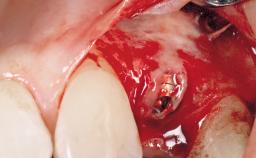

Immediate Placement of an Implant in a Maxillary Right Central Incisor Site

A 30-year-old female patient was referred to the office for the treatment of tooth 11. Her chief concern at the initial visit was to inquire, “Why is my tooth pink?” Upon clinical examination, it was determined that tooth 11 had a previous history of trauma and that the clinical crown had become noticeably pink in color as a result of internal resorption. This diagnosis was confirmed radiographically, indicating a large radiolucency involving the central and distal portions of the clinical crown. It was determined that restoration of this tooth was not possible, and that extraction was indicated. The presence of a mid-line diastema, which the patient wanted to reproduce, directed the treatment plan for tooth replacement utilizing a dental implant.

Placement Protocol Immediate implant placement

Socket Morphology Single-root socket

Socket Integrity Sufficient, with intact bone walls

Bone Volume Sufficient, with intact walls